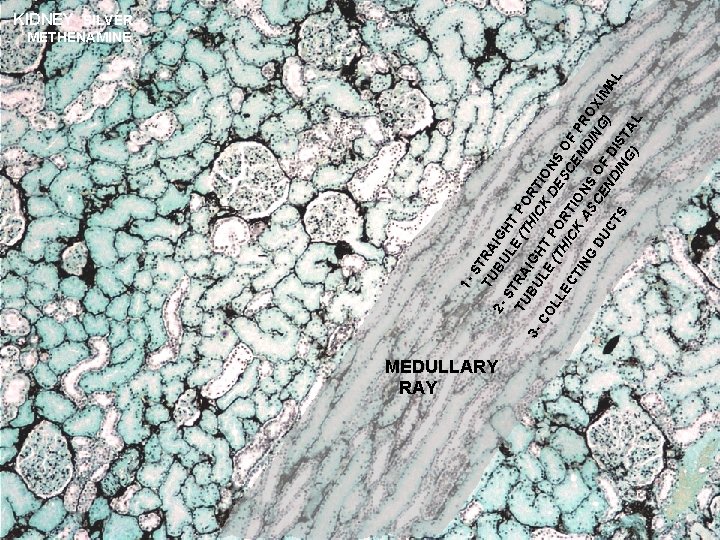

URINARY SYSTEM THE NEPHRON & COLLECTING DUCTS CORTEX: CORTICAL LABYRINTH 1 - RENAL CORPUSCLES 2 - PROXIMAL CONVOLUTED TUBULES 3 - DISTAL CONVOLUTED TUBULES MEDULLARY RAY 1 - STRAIGHT PORTIONS OF PROXIMAL TUBULE (THICK DESCENDING) 2 - STRAIGHT PORTIONS OF DISTAL TUBULE (THICK ASCENDING) 3 - COLLECTING DUCTS

S TU TRA B IG 2 ST ULE HT TU RA (T PO HI RT BU IG 3 CK IO LE HT CO P D N LL (T HI ORT ESC S O EC C I EN F P TI R NG K A ONS SC O DIN OX DU G) IM EN F CT AL D DI IS S NG T ) AL 1 - KIDNEY SILVER METHENAMINE MEDULLARY RAY

URINARY SYSTEMKIDNEY H&E CORTEX: MEDULLARY RAY 1 - STRAIGHT PORTIONS OF PROXIMAL TUBULE (THICK DESCENDING) 2 - STRAIGHT PORTIONS OF DISTAL TUBULE (THICK ASCENDING) TD C 3 - COLLECTING DUCTS - cells are cuboidal in cortex and become progressively more columnar in the medulla and papilla - cells stain very lightly with well-defined boundaries - transport urine from nephron to excretory ducts and aids in further H 2 O resorption in the presence of ADH D C D